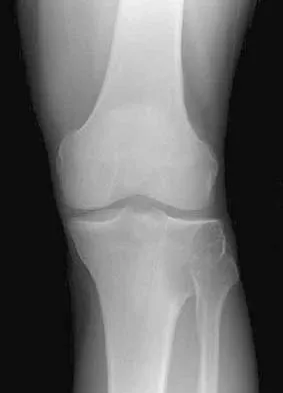

A 75-year-old woman who fell on her right knee now reports pain and is unable to bear weight. History reveals that she underwent total knee arthroplasty on the right knee 6 years ago. Radiographs are shown in Figure 5. Management should now consist of

The radiographs show a loose femoral component with an associated medial condyle distal femoral fracture. The treatment of choice is open reduction and internal fixation with revision of the femoral component because of the femoral component loosening. Moran MC, Brick GW, Sledge CB, et al: Supracondylar femoral fracture following total knee arthroplasty. Clin Orthop 1996;324:196-209. McLaren AC, DuPont JA, Schroeber DC: Open reduction internal fixation of supracondylar fractures above total knee arthroplasties using the intramedullary supracondylar rod. Clin Orthop 1994;302:194-198.